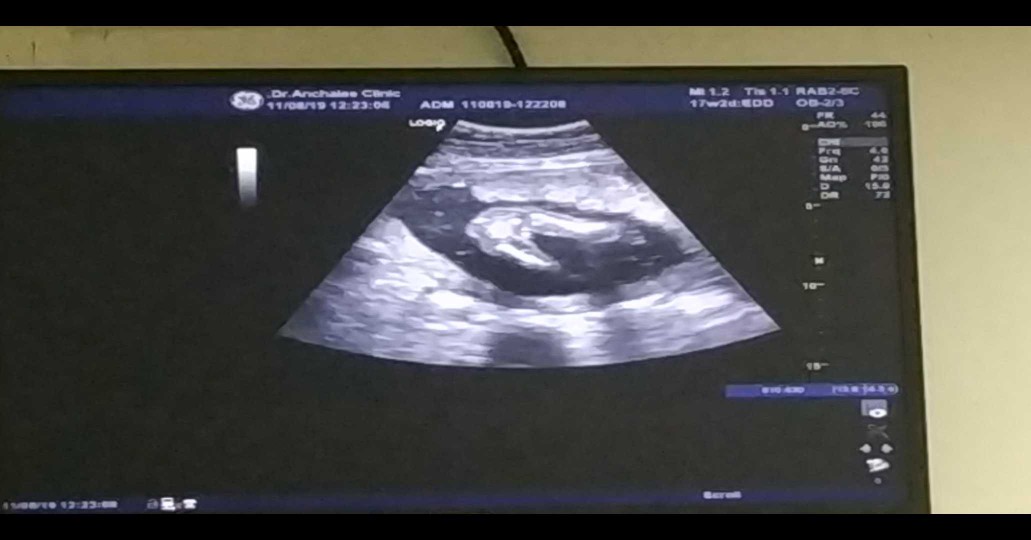

บ้านนี้หมอบอกว่าลูกสาว แม่ๆว่าใช่ไหมค่ะ ☺️?

5มกราจ้า ลูกสาว

17 ม.ค. ลูกสาวค่ะ